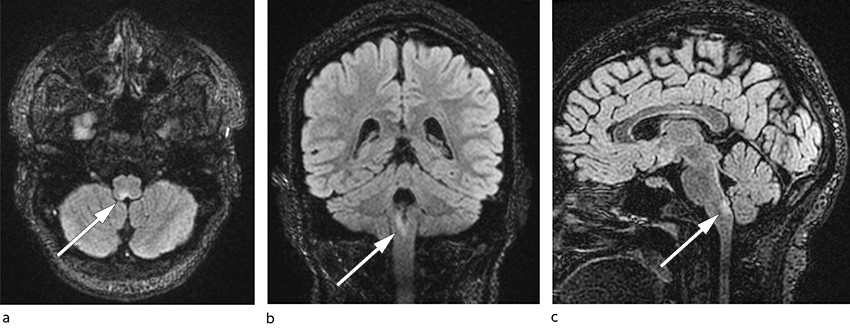

Four days after discharge, the woman was readmitted because of an exacerbation of the problems. The first two days after her discharge she had managed to ingest some food and drink, but then she again experienced acute nausea and vomiting immediately after eating. Clinical biochemical tests were largely unchanged or normalised compared with her first admission: sodium 141 mmol/L, potassium 3.9 mmol/L and slight thrombocytosis 452 × 109/L, but otherwise normal values, including CRP < 1 mg/L, Hb 14.0 g/dL, leukocytes 7.7 × 109/L, ALT 34 U/L, ALP 71 U/L and bilirubin 6 µmol/L. Thirty days after symptom onset a head MRI was performed on suspicion of a central nervous cause of the nausea. A signal change was detected in the medulla oblongata, measuring 4 mm in the axial plane and 11 mm in the craniocaudal direction (Figure 1). It was hyperintense on T2-weighted images, hypointense on T1-weighted images, and had a weak high signal on diffusion-weighted images. The lesion did not enhance with contrast. There were no other pathological signal changes.

In light of the MRI scan, a tentative radiological diagnosis was either subacute phase infarction or demyelinating lesion. The lesion was perceived as the cause of the patient's persistent nausea, vomiting and hiccups, and she was transferred to a hospital with a neurology department. At a clinical neurological examination on admission, 31 days after symptom onset, she was conscious and oriented, and findings on examination of cranial nerves, motility, sensibility and coordination were normal. Her deep tendon reflexes were symmetrically weak. Her gait was normal, and Romberg's test was negative. A secondary examination of the MRI images after her transfer did not rule out a demyelinating disease, and this, coupled with the clinical picture, gave rise to suspicion of neuromyelitis optica spectrum disorder, NMOSD, presenting as so-called area postrema syndrome.